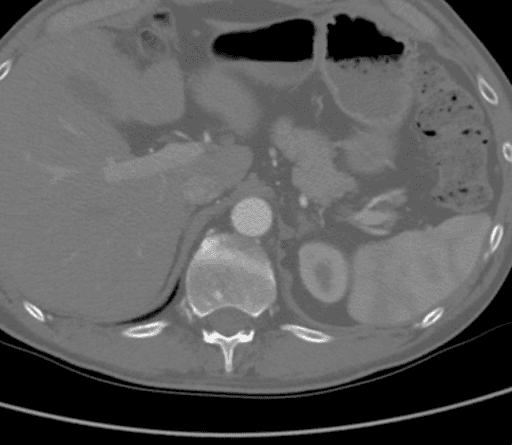

CTA demonstrated a complete aortic occlusion at the level of the bilateral renal arteries from a combination of calcified and soft atherosclerotic plaque. Significantly, in this case, the atheroma extended proximally to the level of the superior mesenteric artery (SMA), as seen in Figure 1, which would have complicated suprarenal clamping and compromised the appropriate inflow for standard aortofemoral bypass (AFB). The supraceliac aorta was free of arterial disease (Figure 2). The occlusion extended to the bilateral common femoral arteries, where flow was reconstituted from the epigastric and circumflex iliac arterial collaterals. The bilateral common femoral arteries (CFA) had atheromatous plaque of approximately 60% stenosis, and then the runoff was intact below the CFA bifurcation.

Figure 1. CTA showing that the atheroma extended proximally to the level of the superior mesenteric artery (SMA), which would have complicated suprarenal clamping and compromised the appropriate inflow for standard AFB.